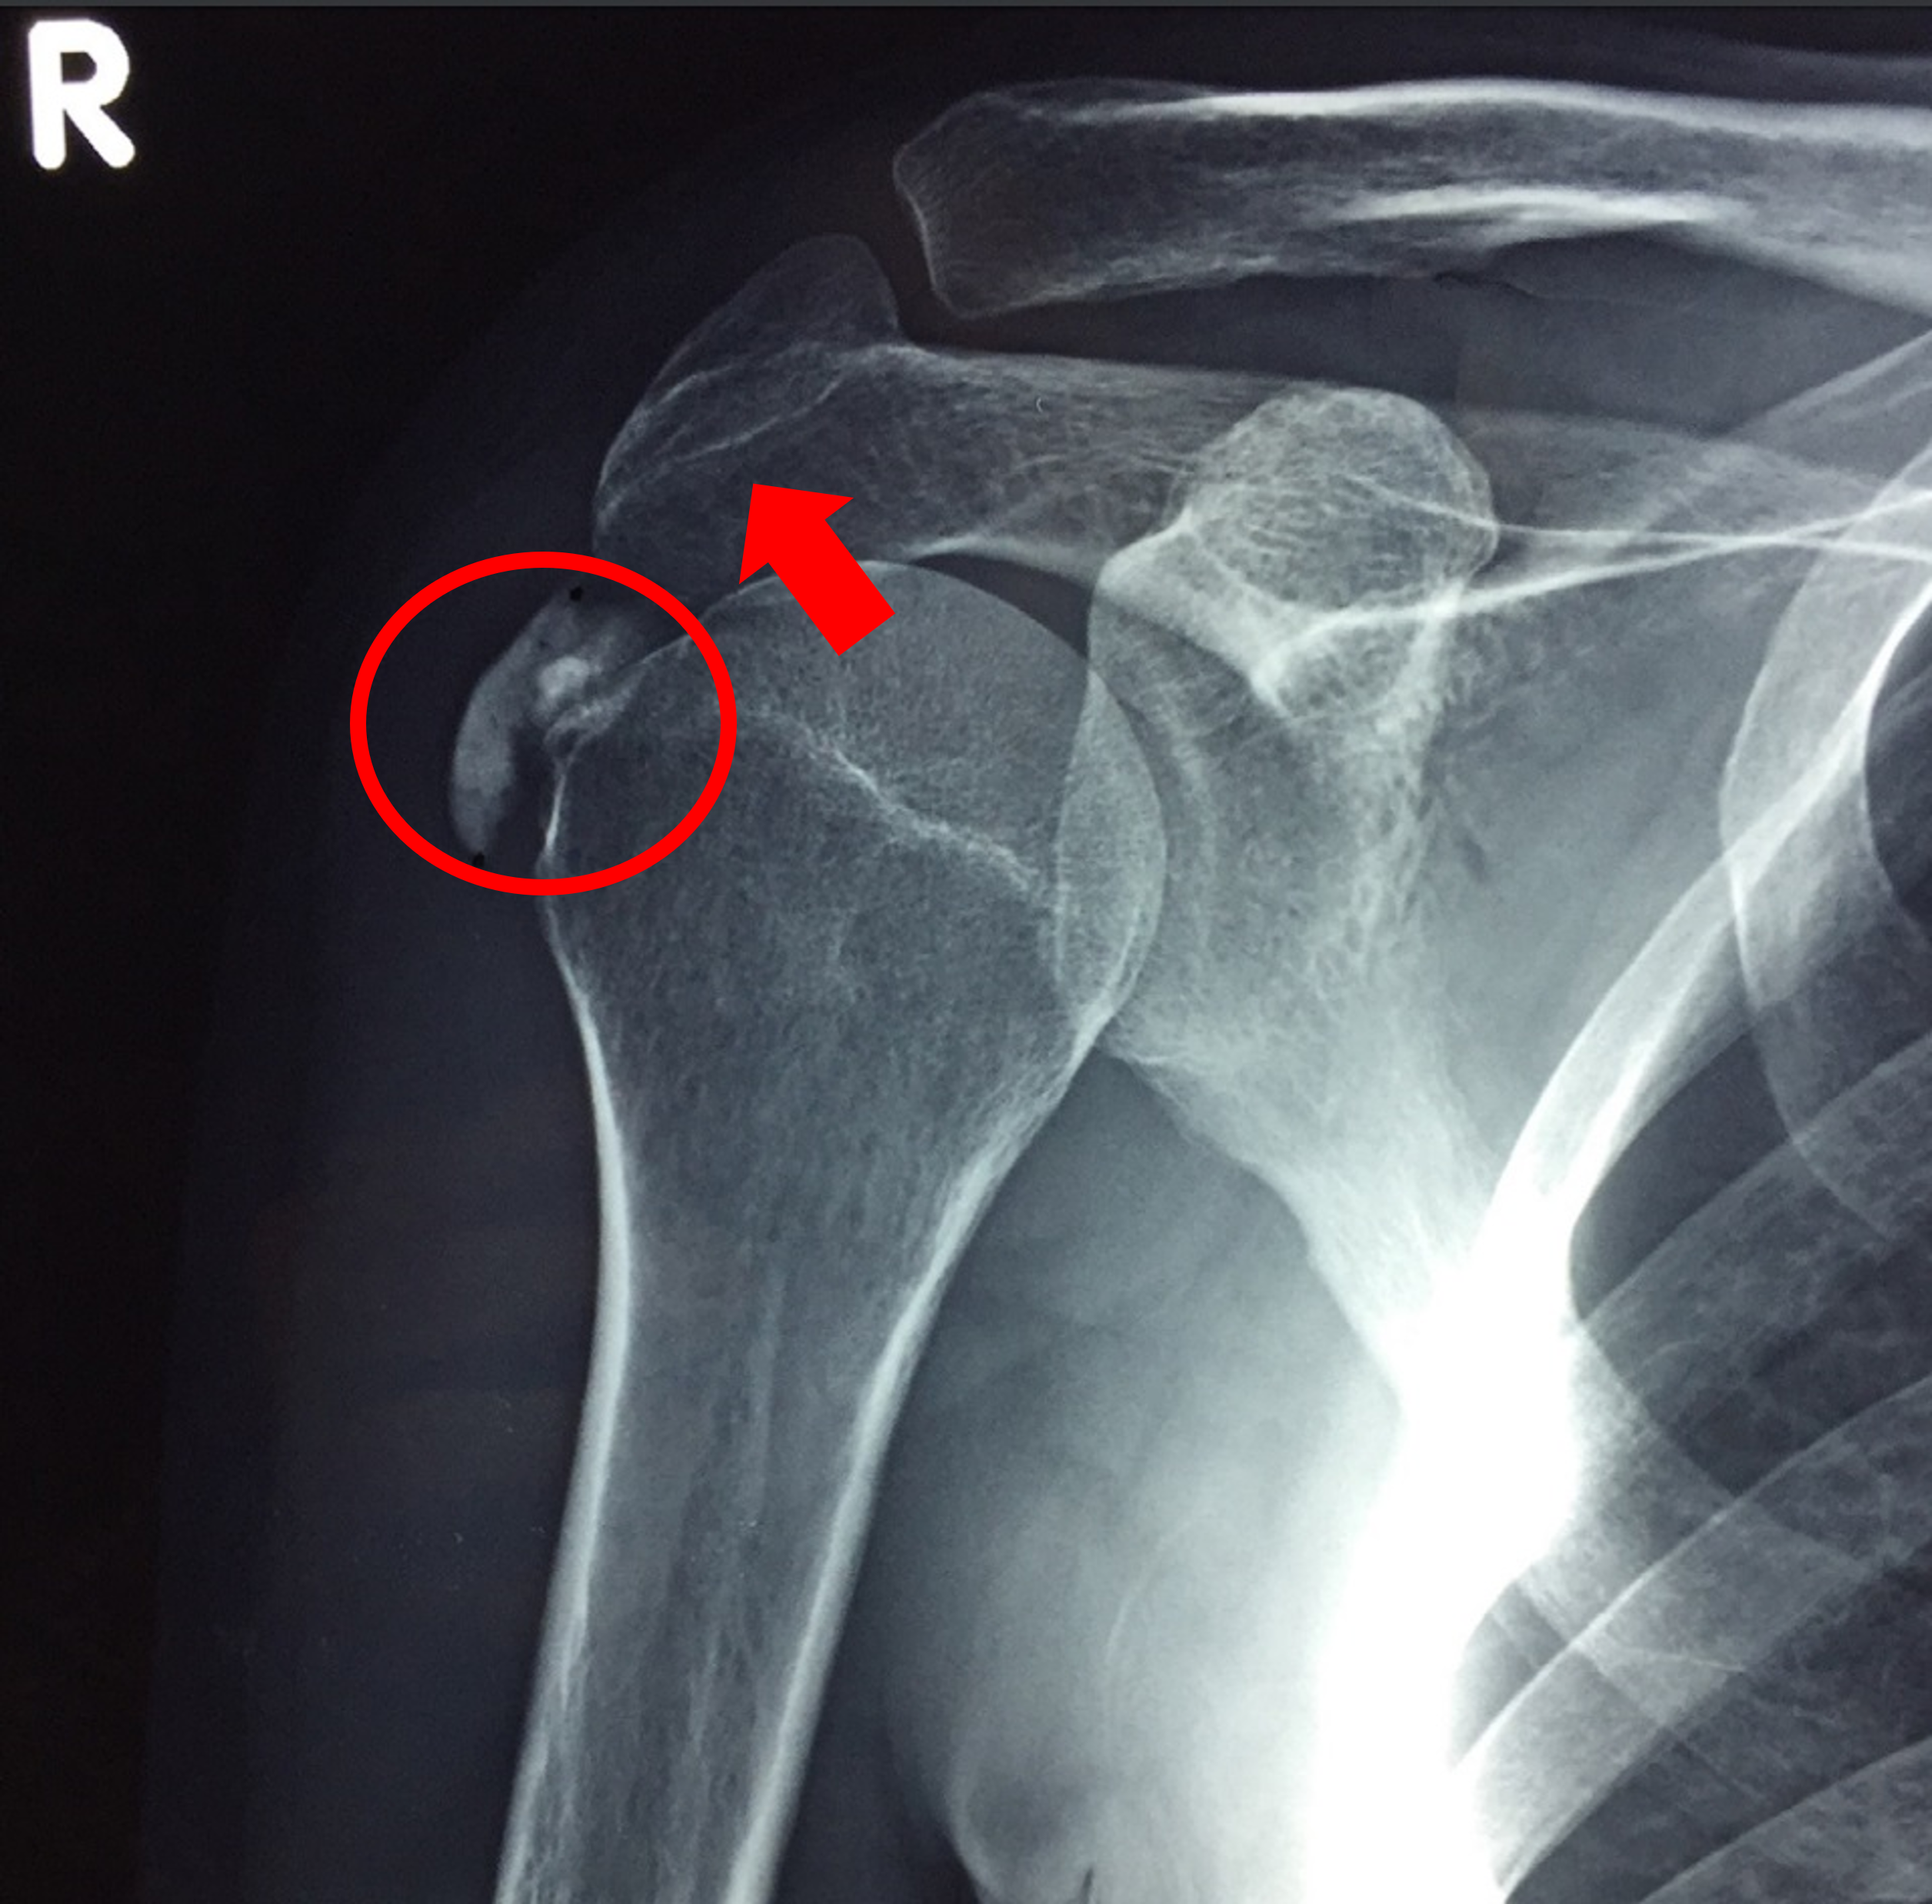

지난 포스팅에서는 처음 들으면 생소한 어깨 관절에 생기는 석회성 건염에 대하여 알아보았습니다. 생각보다 많은 사람들이 겪게되는 질환이지만, 막상 나에게 석회가 생겼다고 하게되면 혼란스럽고 어떻게 해야할지 막막할 수가 있는데요. 이번 포스팅은 지난 시간에 이어서, 그렇다면 내 어깨에 자리잡은 석회를 어떻게하면 제거하고 치료할 수 있는가에 대하여 알아보도록 하겠습니다.

석회성 건염의 치료 목적은 당장의 통증을 감소시키는 것과 형성기-휴지기-용해기라는 어쩔 수 없이 거쳐야 하는 자연적 경과를 앞당겨, 빠른 완치로 이끌어가는 데에 있습니다.

석회성 건염에 체외충격파가 효과가 있다는 것을 이해하는 것이 사실 크게 어려운 일은 아닙니다. 석회 침착물이 모여있는 부위를 초음파로 표시를 하고, 해당 부위를 충격파를 쏴서 파쇄시킨다는 아주 1차원적인 개념으로도 이해가 가능한 방법입니다.